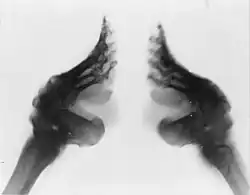

Mutilarea genitală a femeilor

Mutilarea genitală a femeilor (MGF) este definită de Organizația Mondială a Sănătății (OMS) ca fiind procedura care constă în "îndepărtarea parțială sau totală a organelor genitale externe feminine, sau crearea altor leziuni organelor genitale feminine pentru non-motive medicale." [61] Conform unui raport UNICEF 2013, 125 de milioane de femei și fete din Africa și din Orientul Mijlociu s-au confruntat cu MGF.[62] OMS prevede că "procedura nu are beneficii de sănătate pentru fete și femei", iar "procedurile pot provoca sângerări severe și probleme urinare, chisturi, infecții, infertilitate, precum și complicații la naștere cu un risc mai mare de deces al nou-născutului. MGF este recunoscută pe plan internațional ca o încălcare a drepturilor fetelor și femeilor. Această practică reflectă inegalitatea adânc înrădăcinată între sex, și constituie o formă extremă de discriminare împotriva femeilor.[61] Potrivit unui raport UNICEF, țările în care femeile sunt expuse la mutilare genitală cel mai des sunt Somalia (cu 98% dintre femei afectate), Guineea (96%), Djibouti (93%) , Egipt (91%), Eritreea (89%), Mali (89%), Sierra Leone (88%), Sudan (88%), Gambia (76%), Burkina Faso (76%), Etiopia (74%) , Mauritania (69%), Liberia (66%), și Guineea-Bissau (50%).[62]

Mutilarea genitală a femeilor face parte din ritualurile și obiceiurile culturale locale în diferite comunități sau țări din Africa și Orientul Mijlociu. Această practică continuă să existe inclusiv în locuri unde este interzisă de legislația națională. Conform Comitetului Inter-African, MGF este definită ca o "practică tradițională dăunătoare".[63] Datorită globalizării și a imigrației, MGF s-a răspândit dincolo de Africa și Orientul Mijlociu în țări precum Australia, Belgia, Canada, Franța, Noua Zeelandă, SUA, și Marea Britanie [64]